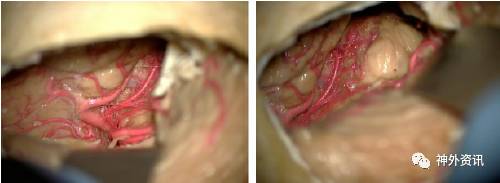

图8. 通过旁正中枕下开颅切除部分左侧小脑幕,显露颞叶底面后部及相关动脉的解剖(左图)。其内侧显示了中脑后外侧的解剖 (右图)。注意,通过此入路显示的大脑后动脉远端分支。